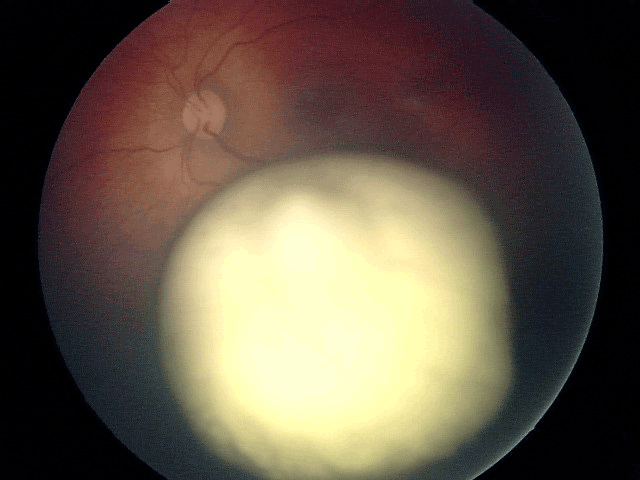

- maladie de Coats : pathologie vasculaire responsable d'une exsudation lipidique très importante pouvant décoller la rétine (Figure 22).

Figure 22 Maladie de Coats, maladie vasculaire rétinienne de l'enfant responsable d'une importante exsudation lipidique sous-rétinienne prenant un aspect « pseudo-tumoral » et pouvant être confondu avec un rétinoblastome.